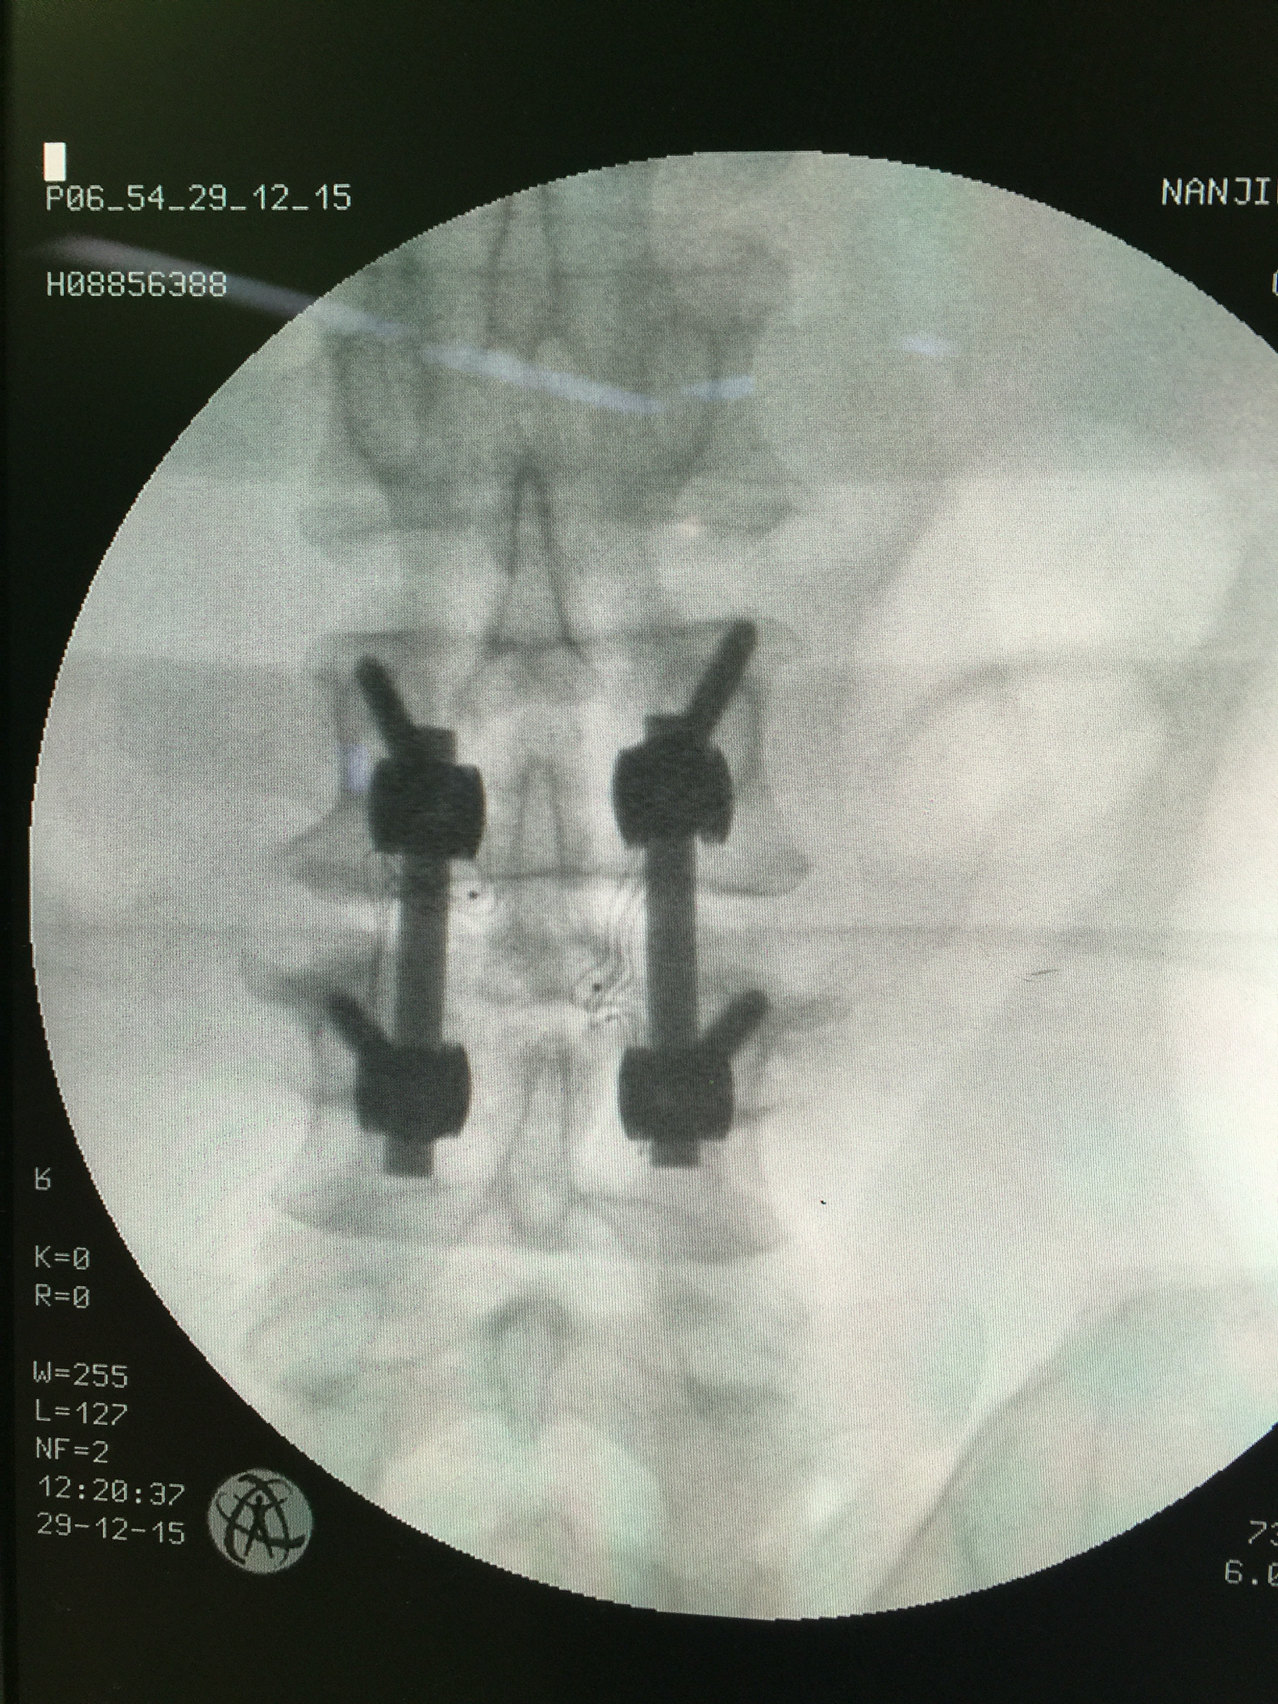

采用2枚3.5皮质骨螺钉固定下胫腓关节,复位满意,内固定位置良好.

下胫腓分离,我们采用过四层骨皮质的单枚螺钉固定.